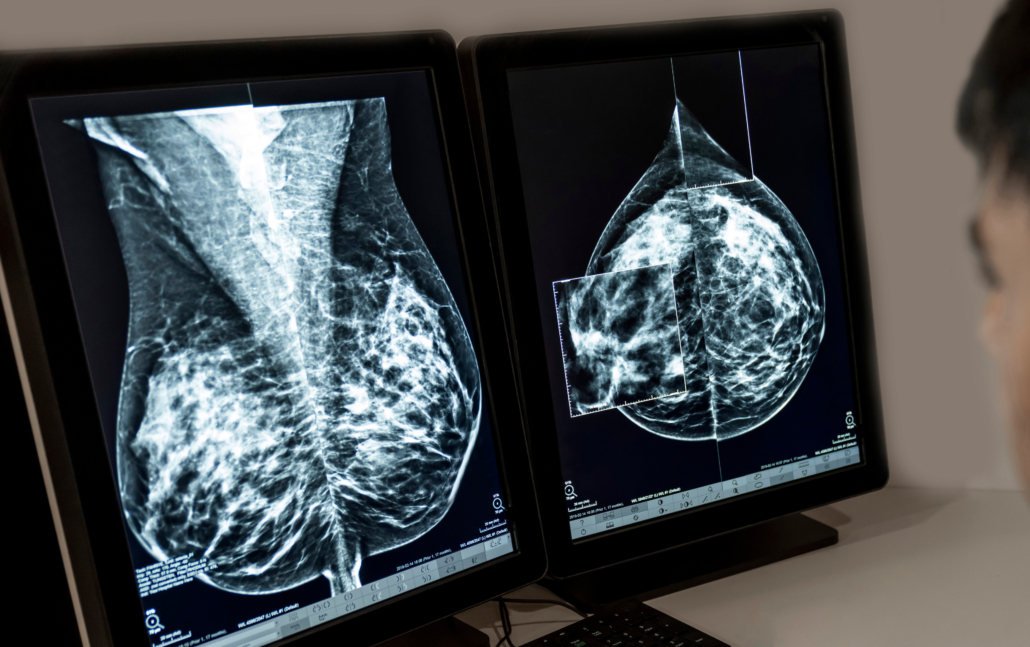

- Dense breasts. Dense breast tissue appears solid white on mammograms and may be more challenging to see through. In most cases, a 3D Screening Mammogram will see suspicious abnormalities that could be breast cancer, but additional imaging may be recommended on a case-by-case basis.

- Difference in priors. Your most recent Screening Mammogram may show changes when compared to prior imaging and additional images may be recommended to see more clearly what those changes are.

- Abnormality. If something appears suspicious, additional imaging or a biopsy of that area may be needed.